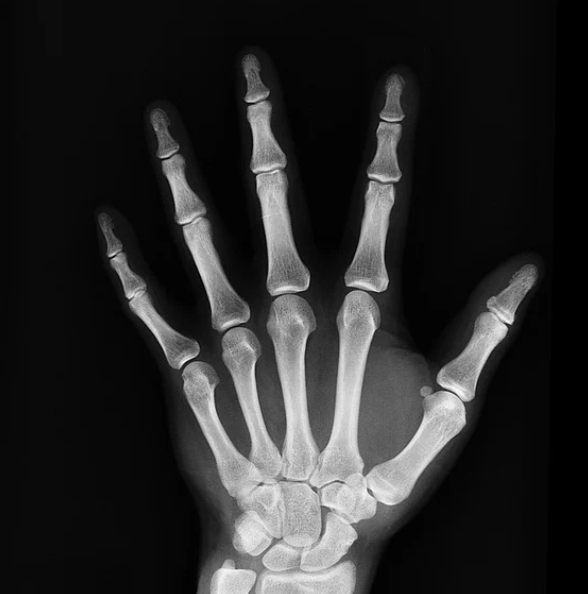

전리방사선 및 비전리방사선의 취급과 방사성동위원소를 이용한 행의학검사와 초음파검사 등 관리 및 취급 업무를 하는 사람을 말합니다. 보통 병원에 가서 엑스레이 검사를 하거나, CT, MRI 검사를 하는 사람들이 방사선사이고, 핵의학과, 방사선종양학과에서 일하는 사람도 방사선사입니다.